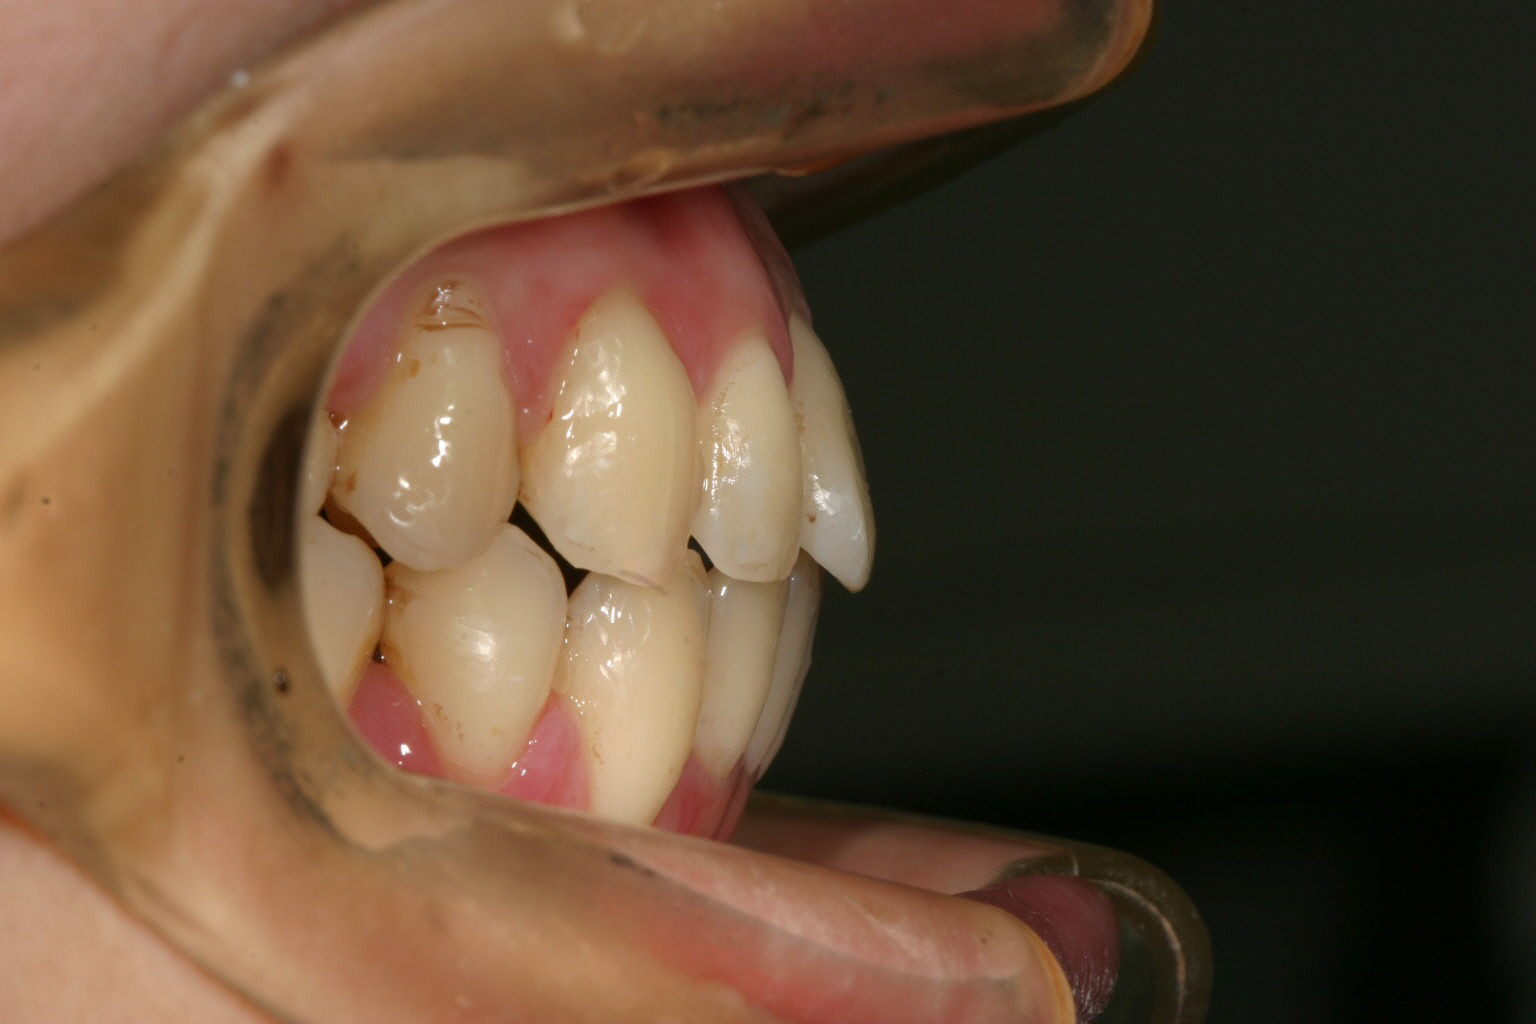

出っ歯観も問題ありません。

綺麗なアーチに改善いたしました。

今回は下顎の叢生がかなり酷いと言う事でワイヤー矯正の方が早いと言う事でワイヤーを選択致しました。

現在では加速矯正装置もあり又インビザラインも進化してますから今でしたらワイヤーでもインビザラインでもと選択肢は両方ありますが

以前のインビザラインはこれだけヘビーな翼状捻転にはかなりの時間を要した為ワイヤーの方がお薦めでした。